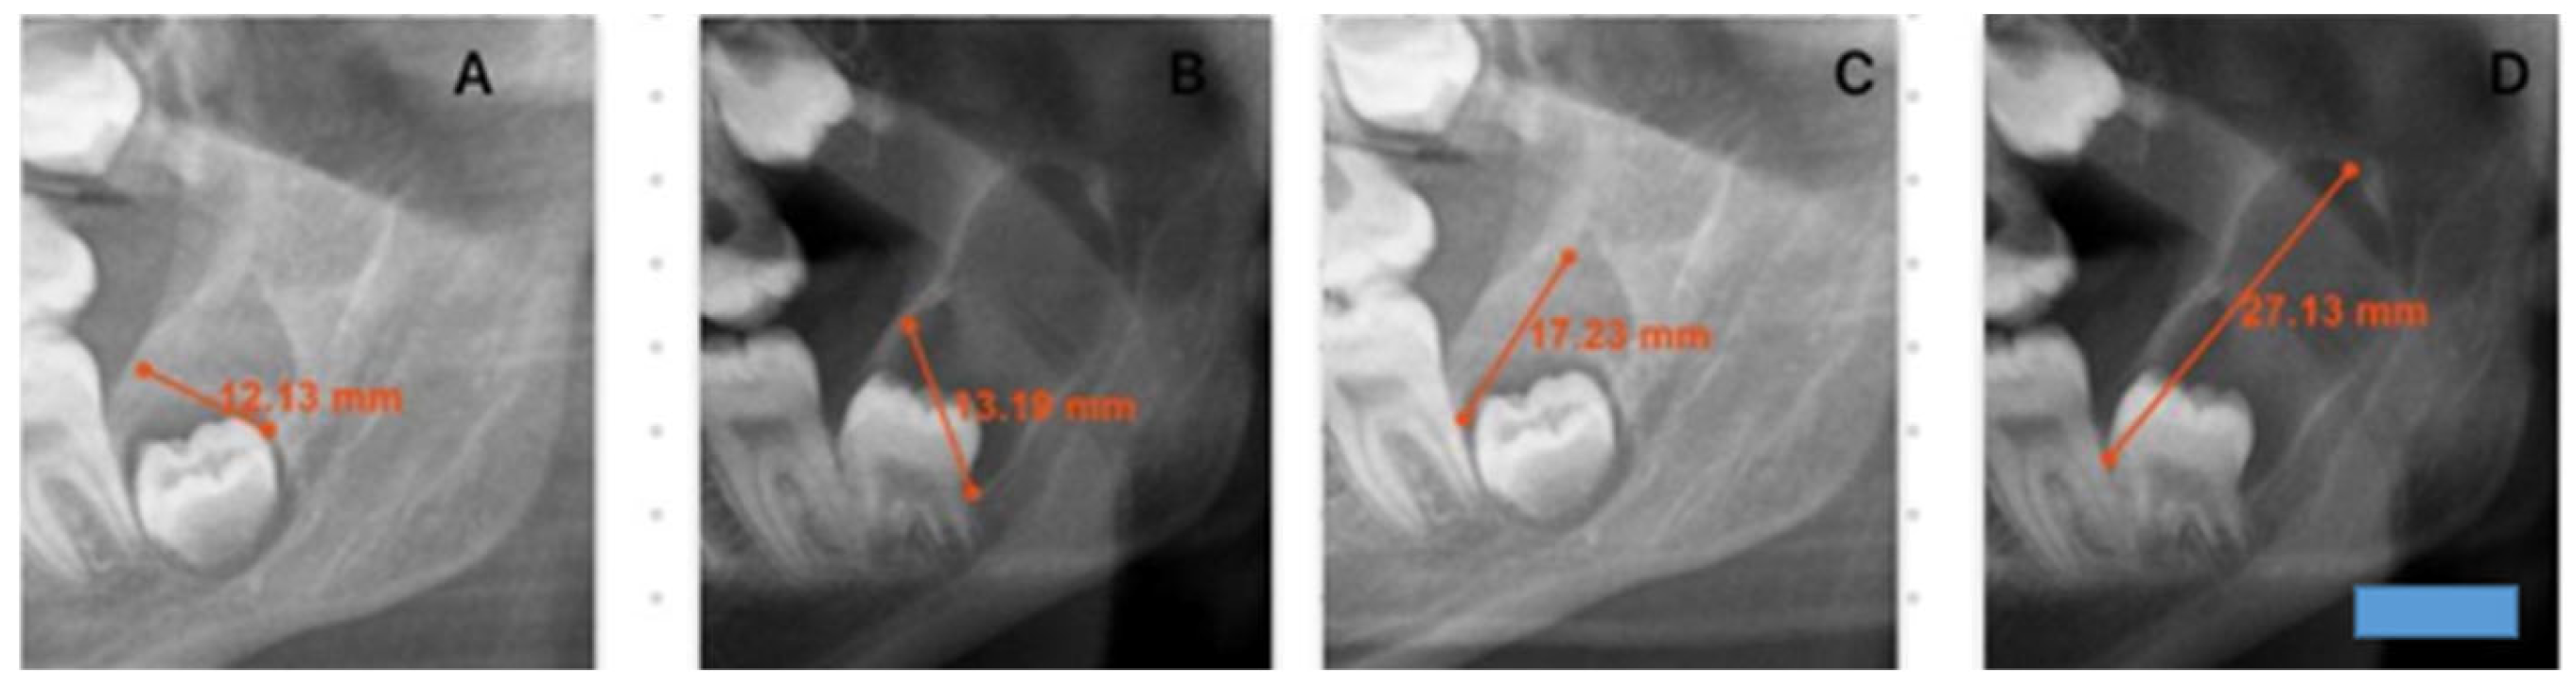

This retrospective study evaluated the radiographic records of patients who presented to the Department of Oral and Maxillofacial Surgery at Dicle University Faculty of Dentistry between 2020 and 2024, underwent biopsy, and received a histopathological diagnosis of dentigerous cysts. Among 187 patients with a definitive post-treatment diagnosis, 12 had previously been scheduled for surgical intervention but failed to attend their appointments (Table 1). Only histopathologically confirmed dentigerous cysts were included in the study. Consequently, radiolucent lesions that could mimic dentigerous cysts were excluded, which inherently limited the scope for comparative analysis. These individuals later returned to the clinic after varying intervals of time. Prior to treatment, new panoramic radiographs were obtained, and repeat biopsies reconfirmed the diagnosis of dentigerous cysts. As patients were informed about the potential risk of neoplastic transformation of these cysts, they were encouraged not to delay treatment, and due to the small number of individuals who postponed their procedures, the sample was limited to 12 patients. To be included in the study, lesions had to remain untreated solely for patient-related reasons, and follow-up panoramic radiographs suitable for comparison had to be available at least six weeks after the initial imaging. In our study, among the included radiographs, the earliest follow-up visit occurred 8 months after the initial radiograph, whereas the latest was recorded 108 months after the initial radiograph. For these 12 patients, the initial panoramic radiographs were compared with follow-up images obtained several months later, focusing specifically on lesions involving the same impacted teeth and corresponding anatomical regions (Figure 1 and Figure 2). Dimensional changes in the cysts over time were measured, and monthly growth rates were subjected to statistical analysis. Only high-quality panoramic radiographs that were clear, properly positioned, and minimally affected by patient-related factors such as movement or improper alignment were included. All images were acquired using devices of the same make, model, and system (Planmeca ProMax 2D (Planmeca Oy, Helsinki, Finland) with DentAssist software (version 4.1.200)), ensuring imaging standardization. The original radiographs were subsequently converted to DICOM format to enable precise digital analysis, and all radiographic measurements were calibrated using the built-in calibration system integrated into the imaging device. In this study, dentigerous cyst lesions were identified on panoramic radiographs, and their dimensions were measured to evaluate changes over time. Because lesion growth rates may differ according to anatomical location, only dentigerous cysts associated with impacted mandibular third molars were included. For each patient, the largest anteroposterior (A–P) and inferosuperior (I–S) dimensions of the cyst were recorded on two panoramic radiographs obtained at different time points. Each dimension was measured twice on every radiograph, and the mean value of the two measurements was used for comparison. All measurements were performed by the same investigator, with each measurement repeated twice to enhance consistency and minimize intra-observer variability. The time intervals between radiographs were standardized and expressed in months for statistical analysis. The monthly growth rate represents a mathematical standardization obtained by dividing the dimensional difference between two radiographs by the elapsed time; it is not intended to directly observe short-term radiological changes.

Figure 1. This figure demonstrates changes in cyst dimensions based on calibrated linear measurements obtained from panoramic radiographs at baseline and at long-term follow-up. The calibrated measurements highlight progressive enlargement over time and provide visual corroboration for the calculated growth rates derived from radiographic length assessments. A blue scale bar with a length of 10 mm and a height of 3 mm was added in the lower right corner of the image. (A): A–P first measurement. (B): A–P second measurement after 64 months. (C): I–S first measurement. (D): I–S second measurement after 64 months.